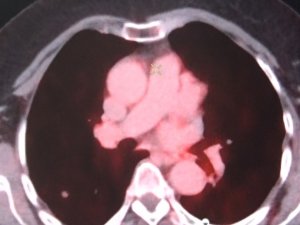

Nedensiz Ateş Ve Terleme Lenfoma İşareti Olabilir

Dünya Lenfoma Farkındalık Günü